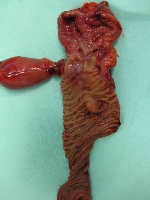

Πρόκειται για γυναίκα ασθενή 70 ετών, η οποία υποβλήθηκε σε αξονική τομογραφία για άτυπα γαστρεντερικά συμπτώματα, εμέτους και απώλεια βάρους. Διαπιστώθηκε συμπαγής μάζα του παγκρέατος, μεγέθους 3 εκατοστών, η οποία εντοπίζονταν στην κεφαλή του οργάνου και βρίσκονταν σε ικανή απόσταση από τα άνω μεσεντέρια αγγεία (εικόνα 1). Η ασθενής έλαβε 4 κύκλους προεγχειρητικής (neoadjuvant) χημειοθεραπείας (gemcitabine, cisplatine, erlotinib). Κατόπιν υποβλήθηκε σε επέμβαση Whipple's (εικόνα 2) με παγκρεατογαστροστομία (εικόνες 3, 4). Στο παρασκεύασμα (με και χωρίς αριστερή εκστροφή της χοληδόχου κύστης) φαίνεται η μάζα (εικόνες 5, 6).